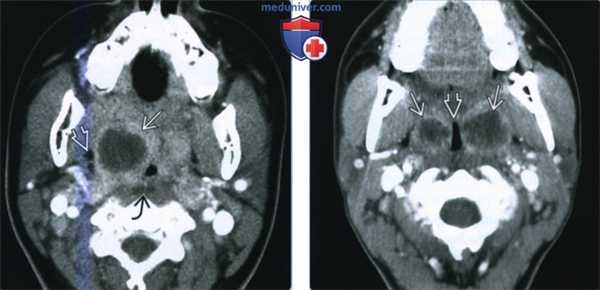

(Слева) КТ с КУ, аксиальная проекция. У ребенка спереди и медиальнее от правой внутренней сонной артерии определяется четко очерченный участок пониженной плотности, который представляет собой нагноившийся заглоточный лимфоузел. Контуры заглоточного пространства сглажены.

(Справа) КТ с КУ, аксиальная проекция, другой пациент. Определяется увеличенный заглоточный лимфоузел с центральным участком пониженной плотности. Имеются воспалительные изменения в области правого сонного влагалища, просвет правой внутренней сонной артерии сужен.

3. КТ при заглоточном абсцессе:

• КТ с КУ:

о Расширение ЗГП за счет скопления содержимого низкой: плотности + накопление контраста в стенках абсцесса:

- На ранних стадиях накопление контрастного вещества может быть незначительным

- Толстые стенки, в которых накапливается контрастное вещество, характерны для зрелого абсцесса

- Предпозвоночные мышцы тоже могут быть отечными

- Газ обнаруживается редко

о Оценить наличие осложнений:

- Нарушение проходимости дыхательных путей

- Достаточно часто встречается сужение просвета внутренней сонной артерии

- Формирование псевдоаневризмы внутренней сонной артерии отмечается редко, говорит об инфицировании метициллин-резистентным S. aureus

- Тромбоз внутренней яремной вены

- Поражение средостения